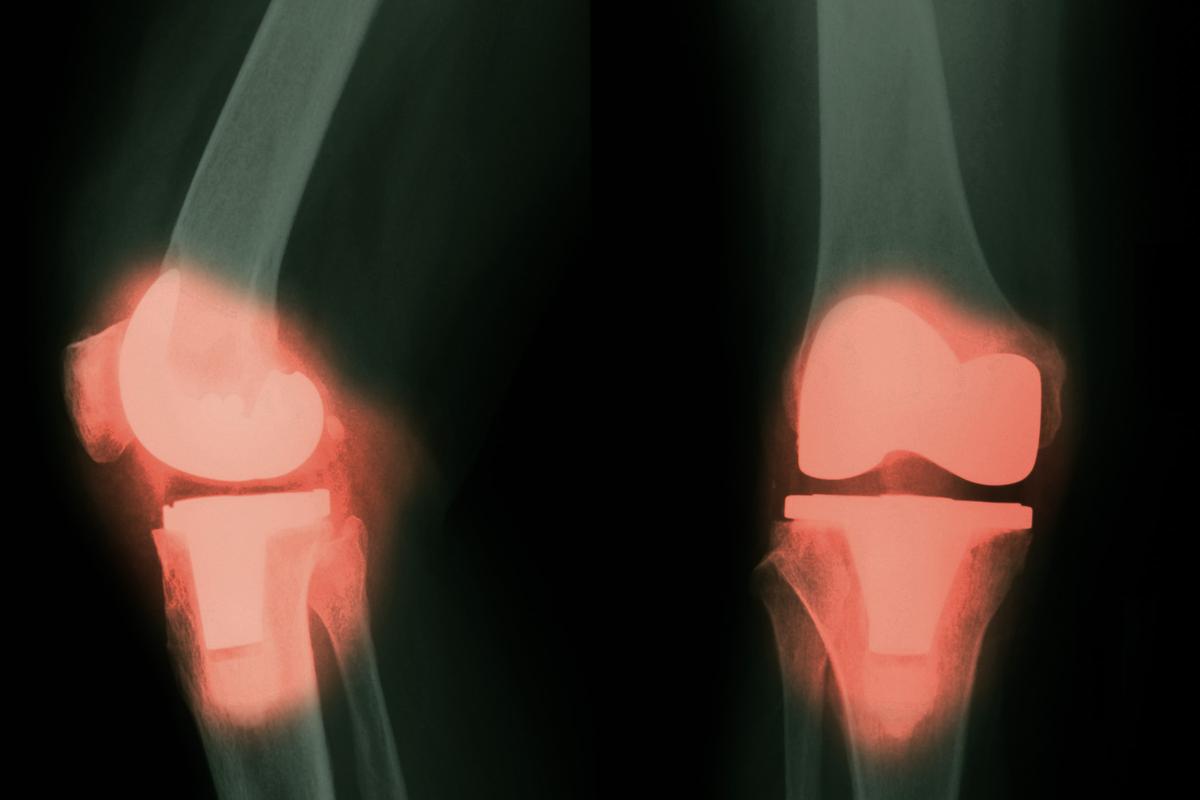

In the United States, approximately 790,000 total knee replacements and 544,000 hip replacements are performed annually, and these numbers are expected to rise as the population ages.